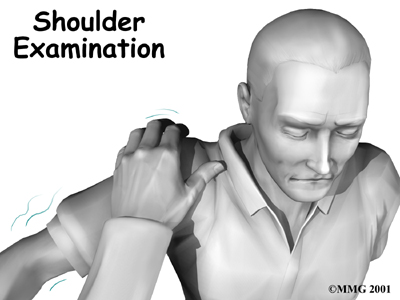

When you visit Ari Levine PT, PC, our physical therapist will diagnose your shoulder instability primarily through your medical history and physical exam.

When you visit Ari Levine PT, PC, our physical therapist will diagnose your shoulder instability primarily through your medical history and physical exam.

The medical history will include many questions about past shoulder injuries, your pain, and the ways your symptoms are affecting your activities.

In the , our physical therapist will feel and move your shoulder, checking it for strength and mobility.

We will stress the shoulder to test the ligaments. When the shoulder is stretched in certain directions, you may get the feeling that the shoulder is going to dislocate.

This is a very important sign of instability. It is called an apprehension sign. (Don't worry. Unless your shoulder is extremely loose, it will not dislocate.)

Some patients may be referred to a doctor for further diagnosis. Once your diagnostic examination is complete, the physical therapists at Ari Levine PT, PC have treatment options that will help speed your recovery, so that you can more quickly return to your active lifestyle.